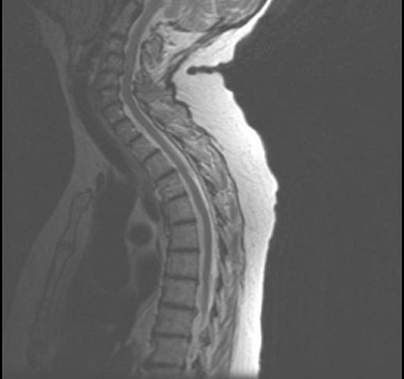

患者,女性,60岁,既往有萎缩性胃炎。因双下肢无力、行走不稳3月来诊。表现精神不振,轻度贫血,双下肢不完全痉挛瘫痪,振动觉、位置觉障碍,行颈髓MRIT项出现如图所示病变。最可能的诊断是()

131、单项选择题

患者,女性,23岁,11天前出现发热、头痛和全身酸痛,近两天出现颈背疼痛,四肢无力,查体四肢肌张力低,腱反射消失,病理征(-),C平面以下痛觉减退,尿潴留,行颈髓MRIT2加权像出现如图所示病变。最可能的诊断是()